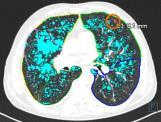

Lung cancer screening Chest CT Pulmonary lesions – Chest X-Ray